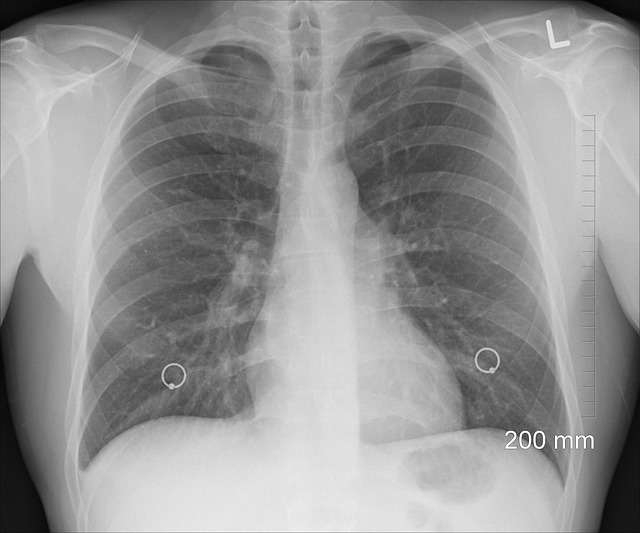

Po roku niepalenia papierosów, nasze płuca zaczynają powoli regenerować się i odzyskiwać swoją naturalną funkcję. Wcześniej, regularne wdychanie dymu tytoniowego powodowało powstawanie szkodliwych substancji chemicznych, które osadzały się w płucach i powodowały uszkodzenia. Po roku bez papierosów, płuca zaczynają oczyszczać się z toksyn, a ich wygląd i funkcja mogą ulec poprawie.

Po roku niepalenia, płuca mogą zacząć wyglądać zdrowsze i czystsze. Usunięcie toksyn z organizmu może prowadzić do zmniejszenia stanów zapalnych w płucach, co może przyczynić się do zmniejszenia kaszlu i duszności. Ponadto, płuca mogą zacząć lepiej funkcjonować, co może prowadzić do zwiększenia wydolności fizycznej.

Po roku niepalenia, płuca mogą również zacząć regenerować się poprzez odbudowę drobnych włókienek, które pomagają w transporcie tlenu do krwi. To może prowadzić do poprawy ogólnego stanu zdrowia i samopoczucia.